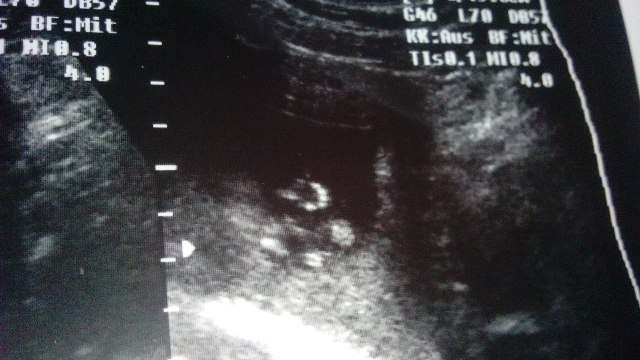

(наша ладошка)

11 недель и 6 дней (на 1 день опережаем срок)

КТР - 4,68

СБ - + 160 уд/м